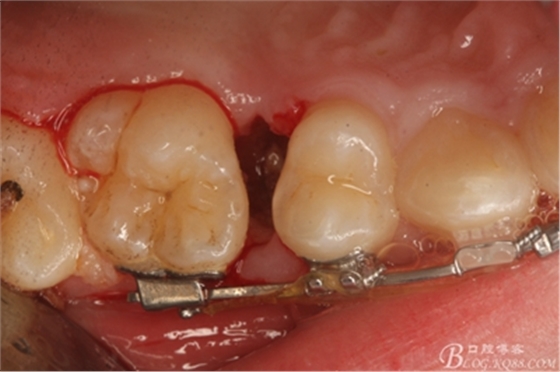

圖10.去除牙齦組織后。露出15牙根斷面,合面無(wú)法脫位